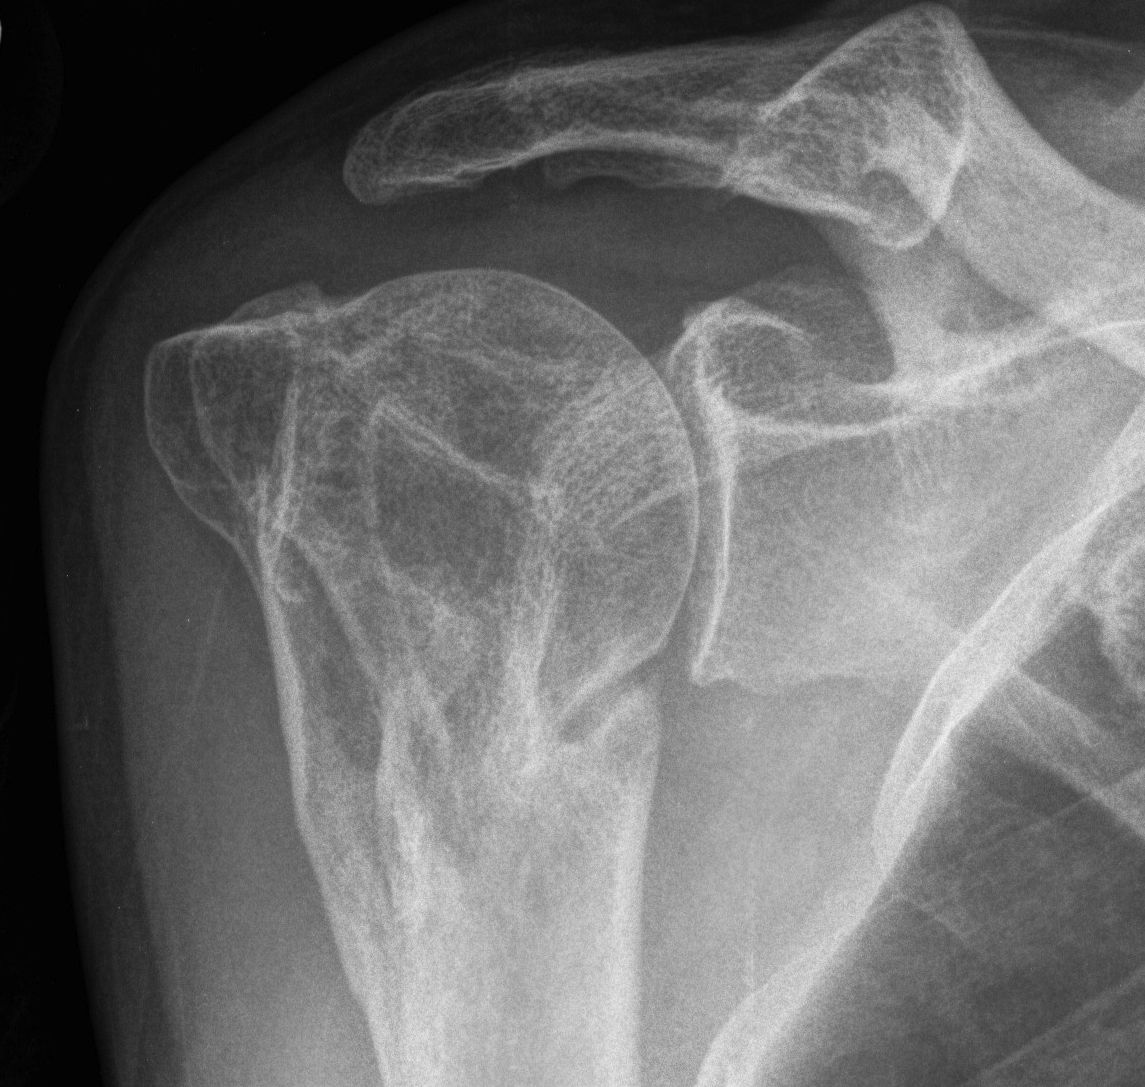

proximal humerus fracture Background ORIF with locking plate Arthroplasty Greater tuberosity fractures Lesser tuberosity fractures / avulsions Book traversal links for Proximal humerus fractures ‹ Pectoralis Major Tears Up Background ›